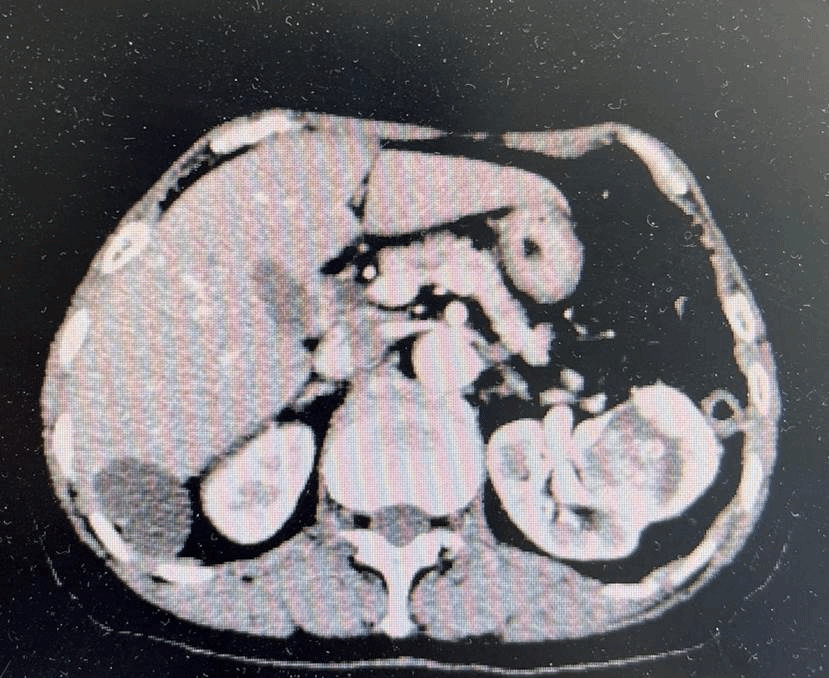

68岁的黄女士因感染新冠病毒导致肺炎来到ac米兰官网中文网站一院治疗。入院后,完善相关检查发现左肾和直肠两处脏器分别有原发占位性病变,需要尽快手术治疗。

左肾占位

泌尿外科三病房副主任刘赞教授介绍,两处脏器原发占位性病变,从安全的角度看要准备二期手术,即先切除肾脏肿瘤后,待患者身体恢复再行直肠肿瘤切除术。但分两次根治患者的肿瘤,对患者的身体和家庭都会造成很大负担,而且不及时切除直肠上的肿瘤,如果出现快速增大或转移到其他部位,对患者的生命健康就会造成更严重的威胁。且在疫情期间,多次往返医院治疗,也会增高再次感染新冠病毒的几率。